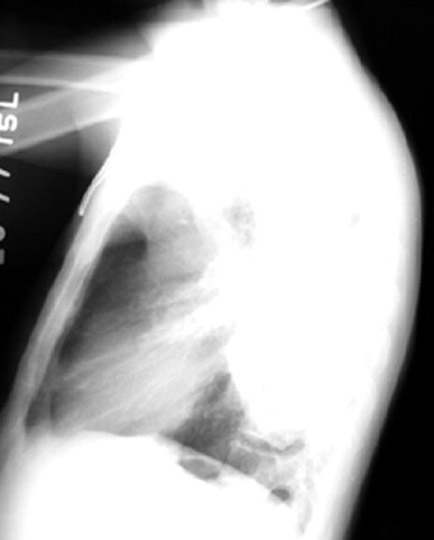

47 year old alcoholic presented with fever, cough and weight loss of 3 weeks duration.  History of 40 pack years of smoking.

Findings:

• Superior segment RLL dense pneumonia

• Note the progression  / Cavity / Complete clearance

• Necrotizing pneumonia

Aspiration Lung Abscess